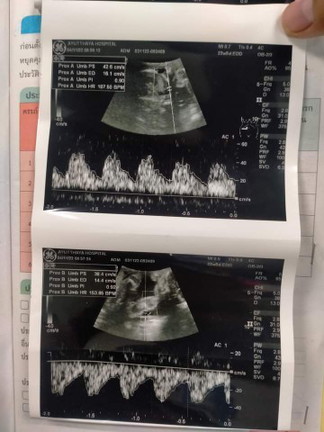

อยากทราบว่า เราดูน้ำหนักของเด็กยังไงค่ะ#ขอบคุณล่วงหน้านะคะ #ท้องแรกคะ #เด็กแฝด ความเสี่ยงสูง

ยุข้างขวามือค่ะแม่ มันจะเขียนภาษาอังกฤษว่า กรัม

อักษรย่อตัว G ทางขวาค่ะแม่